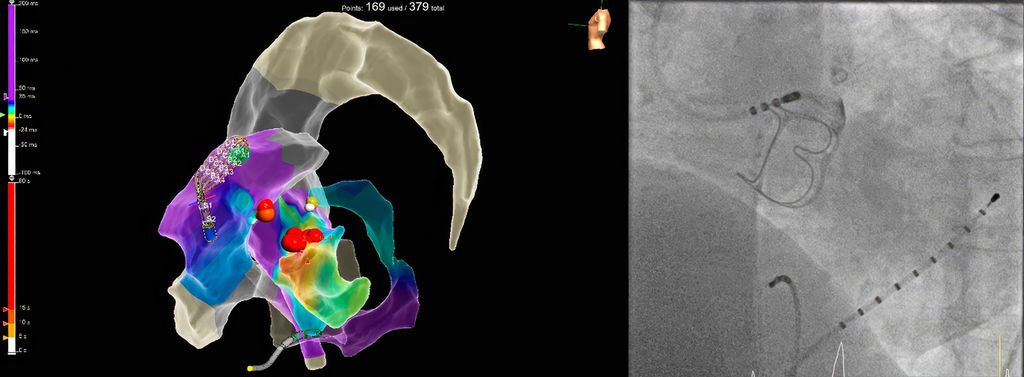

Die Katheterablation von symptomatischen ventrikulären Extrasystolen (VES) oder monomorphen ventrikulären Tachykardien (VT) ohne zugrunde liegende strukturelle Herzerkrankung stellt laut aktuellen ESC-Leitlinien6 im Falle von aus dem rechtsventrikulären Ausflusstrakt (RVOT) kommenden Arrhythmien oder faszikulären Tachykardien eine Klasse-I-Indikation dar. Bei anderen idiopathischen VES/VT-Lokalisationen, z.B. aus dem linksventrikulären Ausflusstrakt (LVOT) entspringenden ventrikulären Arrhyth-mien, ist zunächst ein medikamentöser Therapieversuch mittels Betablockern oder Kalziumkanalblockern indiziert (Klasse-I-Empfehlung), bevor eine Katheterablation in Erwägung gezogen wird (Klasse-IIa-Empfehlung). Dies ist durch die doch komplexere Ablationsprozedur bedingt, da insbesondere LVOT-Arrhythmien oftmals einer Katheterablation schwerer zugänglich sind (Fokus im Aortensinus, im distalen Koronarsinus/„great cardiac vein“). Gegebenenfalls kann ein Ablationsverfahren von mehreren Herzhöhlen ausgehend notwendig sein, entweder konsekutiv (Abb. 2) oder mittels bipolarer Ablation, wo mithilfe eines speziellen Generators die gleichzeitige Energieabgabe über zwei Katheter simultan erfolgen kann.7

Abb. 2: Links: 3D-Rekonstruktion und Aktivierungsmapping mittels multipolaren Mapping-Katheters und erfolgreiche Ablation einer ventrikulären Extrasystolie vom „left ventricular summit“ mittels konsekutiver Energieabgabe im rechtsventrikulären Ausflusstrakt (links im Bild) und linksventrikulären Ausflusstrakt/Aortensinus (mittig – rote Punkte) sowie im distalen Koronarsinus am Übergang zur „great cardiac vein“ (gelber Punkt). Rechts: Kontrastmitteldarstellung des linkskoronaren Aortensinus mittels Kontrastmittelgabe über den Ablationskatheter vor Ablation (unmittelbare Nähe zum Abgang des linken Hauptstamms und zum biologischen Aortenklappenersatz)